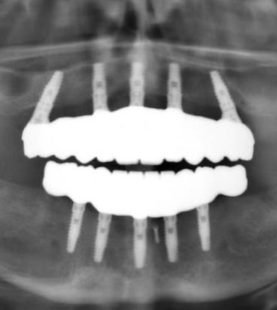

Anterior Implant Prosthetics

- Anterior implant prosthetics

- Implant positioning concepts and guidelines

- Digital implant planning – step-by-step to surgery and immediate loading